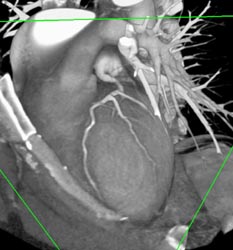

RCA Off of Left Cusp